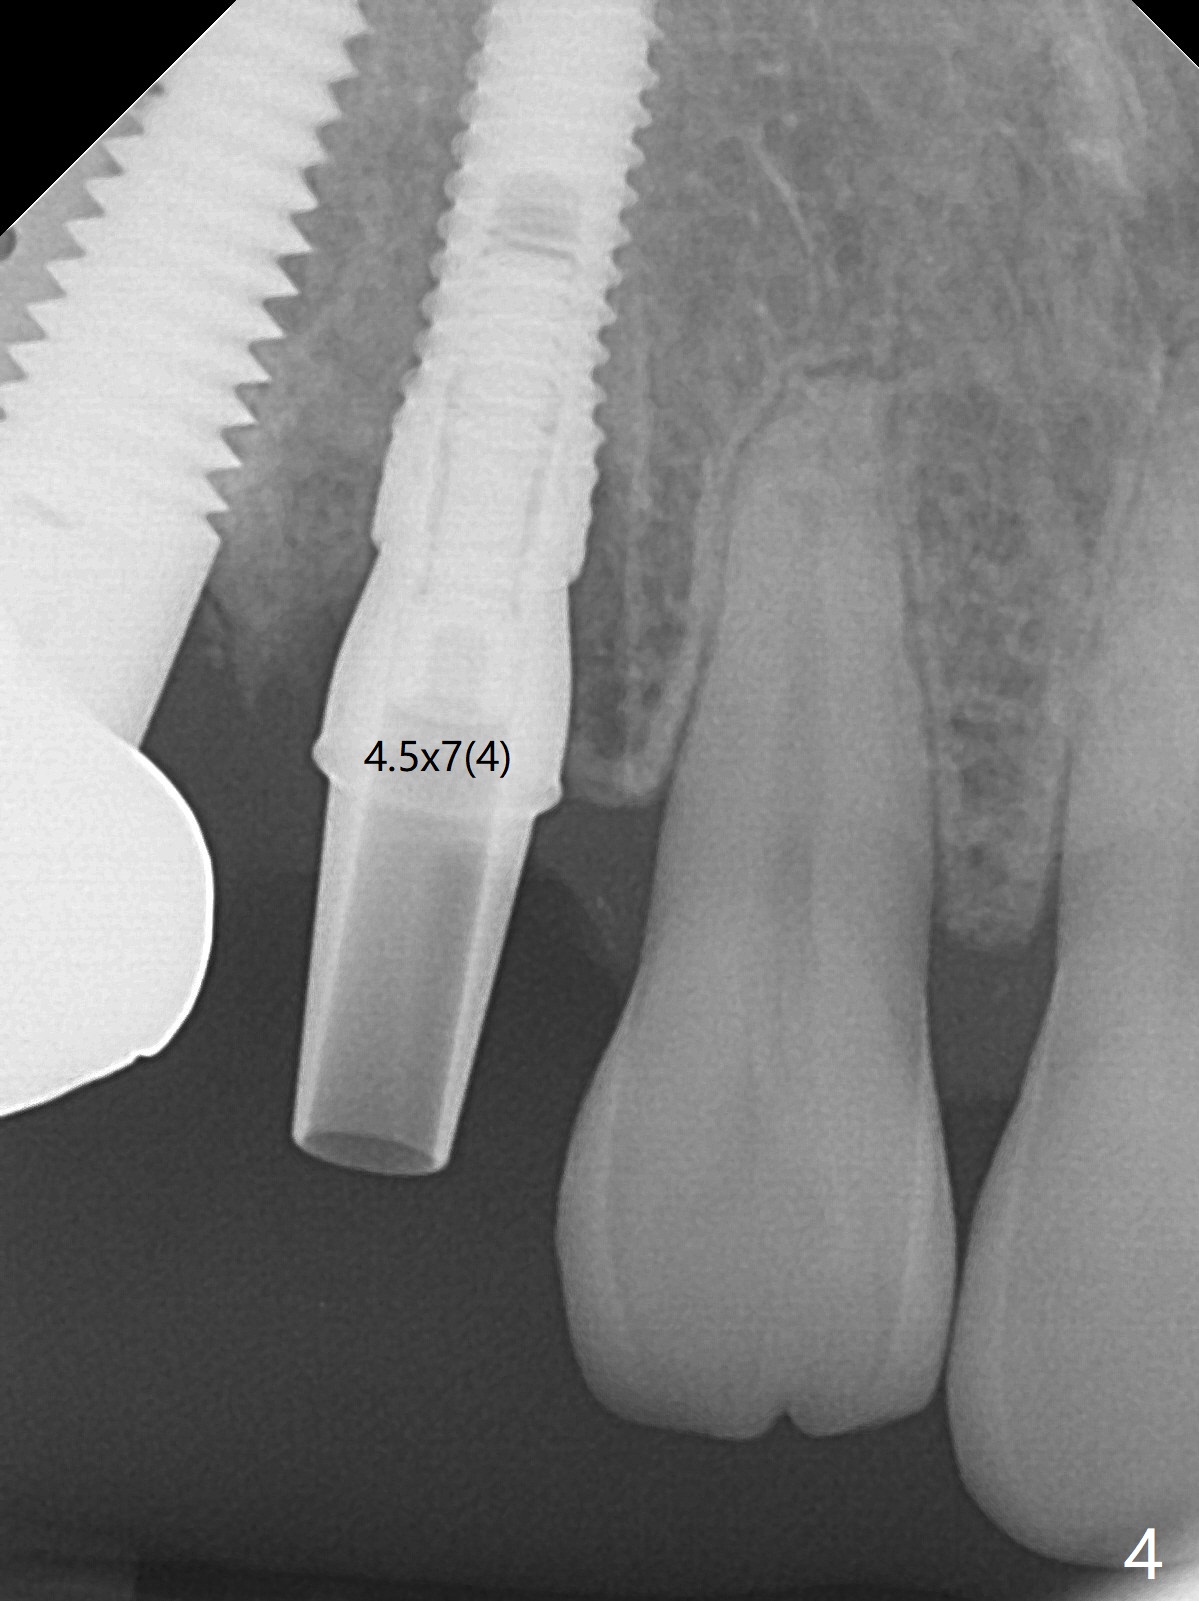

When the recemented crown at #6 is removed, the post is found to have been fractured. When the tooth is extracted, the socket walls are found intact. After moving the initial osteotomy (Fig.1) mesial, a 3.8x13 mm implant is placed (Fig.2). Clinically it appears supracrestal lingually. So the implant is placed deeper, but a cemented abutment is incompletely seated (Fig.3 <). When a longer abutment is used (easy grasping), it is seated completely (Fig.4). Then sticky bone is packed (Fig.5 *). When an immediate provisional is fabricated and seated, PRF membranes are inserted into the remaining gap between the gingiva and the provisional. Free hand surgery takes time and more intraop X-ray. It is inconvenient with nervous patients. The socket heals 2 weeks postop (Fig.6). The provisional will be next relined and reseated. It is difficult to insert gingival retraction cord 3.5 months postop because of the deep mesial margin. When an abutment with longer cuff is placed, the packing is easier (no biologic width violation, Fig.7 (^: resorbed mesial crest), as compared to Fig.5). When the crown is cemented (un-esthetic due to failure of use of temporary abutment), the metal shows at #5 with gingival recession because of buccal placement (Fig.8-10). Bone resorption is severe between #5 and 6 (Fig.7), as related to large gingival embrasure (Fig.9 *). When #5 crow is redone, move the gingival margin apical and fabricate provisional.